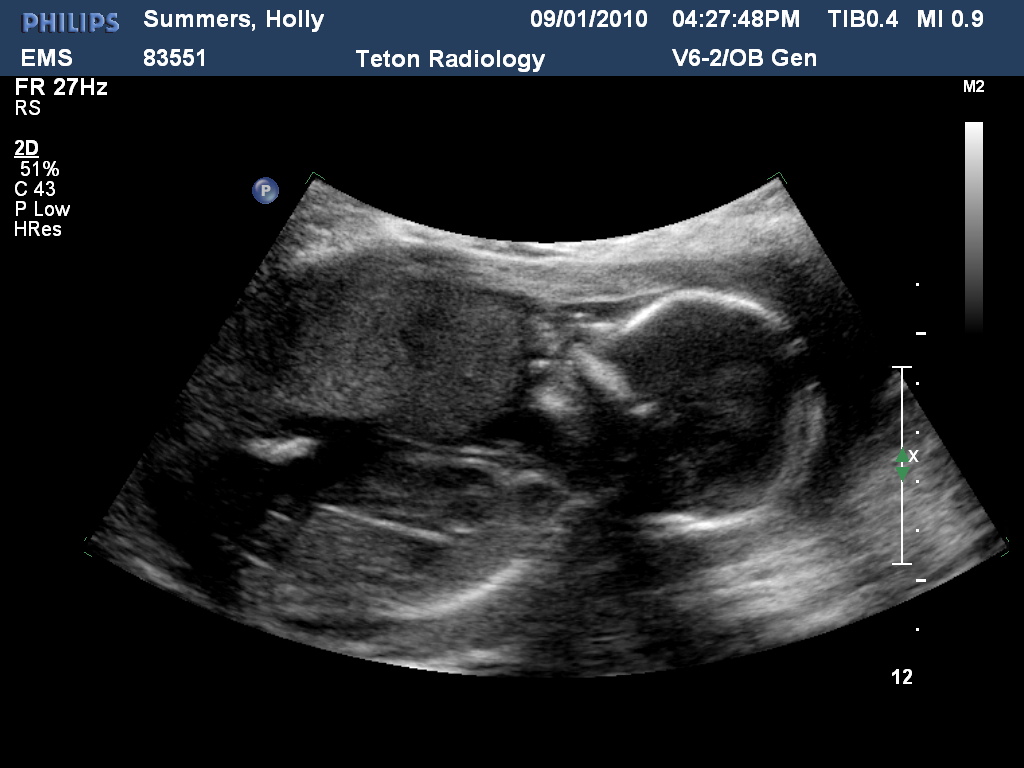

So, as always things are not ever perfect. The baby wouldn't give a really good look down below. What the tech saw looked like girl. She didn't see that tell tell boy. So, she said she is 85% sure it is a girl. The baby gave some other really good side profile shots though that made me so happy to see her little body moving inside me. She also had her hand up like she was waving. Very cute. Then she looked like she started to suck her thumb which surprised Ryan cause he didn't know they could do that this young. I love that modern technology has evolved so much that we can see every thing and know that the baby is doing good and is developing right on track. Another girl will be easy because yes, I do already have a lot I can reuse. The only problem is that they will be born in opposite seasons, so I will have to still do some clothes shopping. Oh Darn. :)